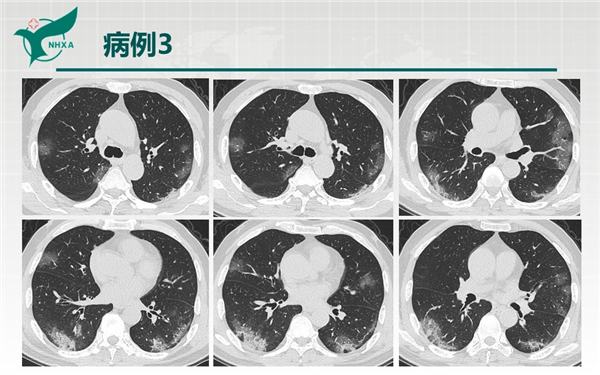

【病例分享】新型冠狀病毒肺炎3例(西安市第九醫(yī)院)

幻燈片10.jpg